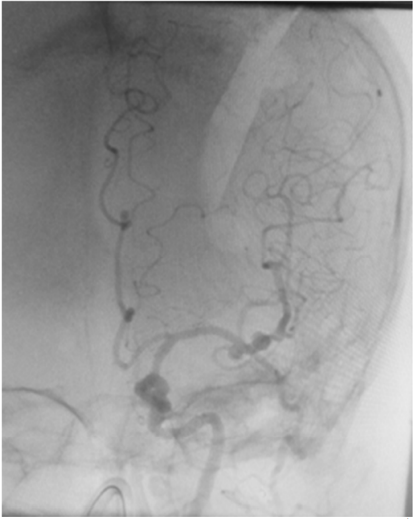

Uma paciente de 66 anos de idade, tabagista, hipertensa com tratamento irregular. Apresentou cefaleia súbita de severa intensidade associada a náuseas. Ao exame físico, observaramse AC = RR2T com BNF, FC = 100 bpm, AP = MVF sem RA, FR = 15 irpm, PA = 182 mmHg x 100 mmHg, SatO2 em ar ambiente = 97%, Glasgow 15, pupilas isofotorreagentes, sem deficits focais. TC crânio e arteriografia a seguir.

Fonte: Acervo pessoal.

Acerca desse caso clínico e com base nos conhecimentos médicos correlatos, julgue os itens a seguir.

O risco de ruptura transoperatória do aneurisma roto da paciente é maior em uma cirurgia tardia quando comparado com a cirurgia precoce.

Apenas um dos aneurismas evidenciados na angiografia pode ser acessado pelo acesso pterional.